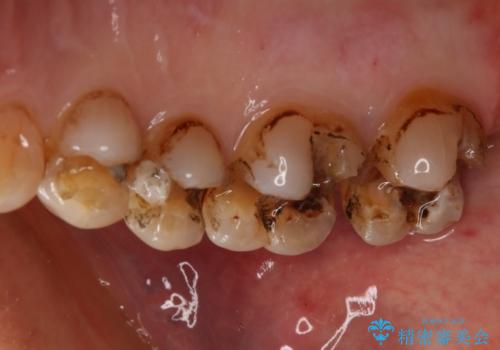

- かなり昔に入れた銀歯の部分のチェックをご希望でご来院されました。

上下ともに銀歯が多く入っており、その下に虫歯が疑われる状態でした。

詰め物の大きさや虫歯の状態から個々に材料と治療範囲を決定し治療に入りました。